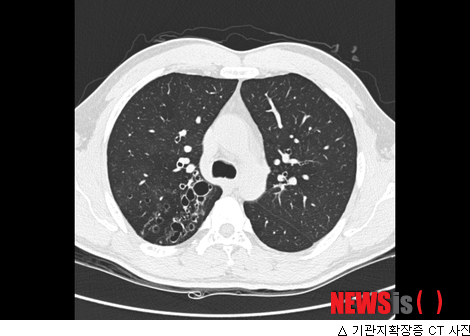

진단 결과 유씨의 병명은 기관지확장증이었다. 반복되는 기관지 염증으로 기관지가 늘어나고 파괴되어 기능을 잃게 되는 질환이다.

이 질환은 어릴 때 폐렴을 앓고 적절한 치료를 받지 못했거나 아동기에 백일해를 앓은 경우, 결핵을 앓은 경우, 또 유독가스를 흡입한 것이 원인이 될 수 있다. 대표적인 증상은 유씨와 같이 기침, 가래, 객혈이 있거나 심해지면 호흡곤란, 청색증이 동반되기도 한다.